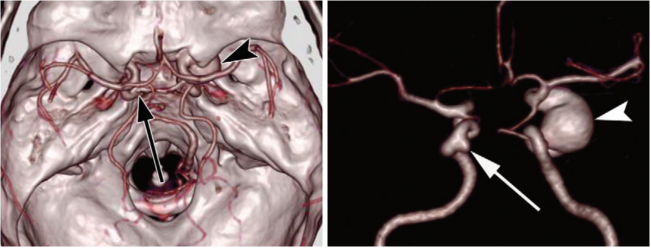

病例三 男,66歲, 突發(fā)頭痛30分鐘, 顱內(nèi)多發(fā)小動(dòng)脈瘤。

CT平掃可見(jiàn)顱內(nèi)左側(cè)小腦區(qū)有環(huán)形高密度影,CTA- MIP中顯示左小腦后下動(dòng)脈瘤, 直徑 約3 mm(黃箭頭所指)

VR圖像中清晰可見(jiàn)前交通動(dòng)脈處小動(dòng)脈瘤1直徑約2mm(紅箭頭所指)

有文章指出, 減影容積CT血管成像對(duì)于檢測(cè)腦動(dòng)脈瘤(3 - 8 mm)的敏感性: 大于8毫米為95 . 6 %左右, 而對(duì)于小于3毫米的微動(dòng)脈瘤卻很容易漏診。

640層寬體探測(cè)器CT擁有0 . 5 mm層厚的探測(cè)器單元, 對(duì)于細(xì)小的病變能夠清晰顯示,大大提高了對(duì)微動(dòng)脈瘤的檢出率。